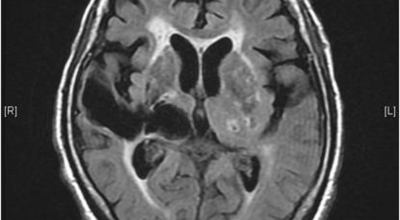

뇌출혈 전조증상을 놓쳐 뇌출혈이 발생하게 되면 발작 직후 안정을 취해야 합니다. 뇌부종을 가라앉히기 위해 약물 요법으로 고농도 포도당, 덱사메타존, 만니톨 등을 투약할 수 있고 뇌의 혈액 순환을 회복시키는 주사와 지혈제, 진정제 등을 사용할 수 있습니다. 혈종의 크기가 중등도 이상으로 마비 증세가 있으면 머리뼈에 작은 구멍을 내서 관을 넣어 혈종을 뽑아내는 수술을 시행할 수 있습니다.

혈압성 뇌출혈인 경우 혈종의 크기가 작으며 환자의 증상이 경미하면 약물 치료를 시행합니다. 혈종의 크기가 매우 크며 뇌가 심하게 부어오를 때는 응급으로 머리뼈를 절개해 혈종을 빠르게 제거해야합니다. 응급조치가 늦어지면 뇌압이 상승해 의식을 잃고 사망에 이를 수 있기 때문인데요 이렇게 증상이 심할 때는 수술이 잘 되었더라도 예후가 좋지 못할 때가 많다고 합니다.